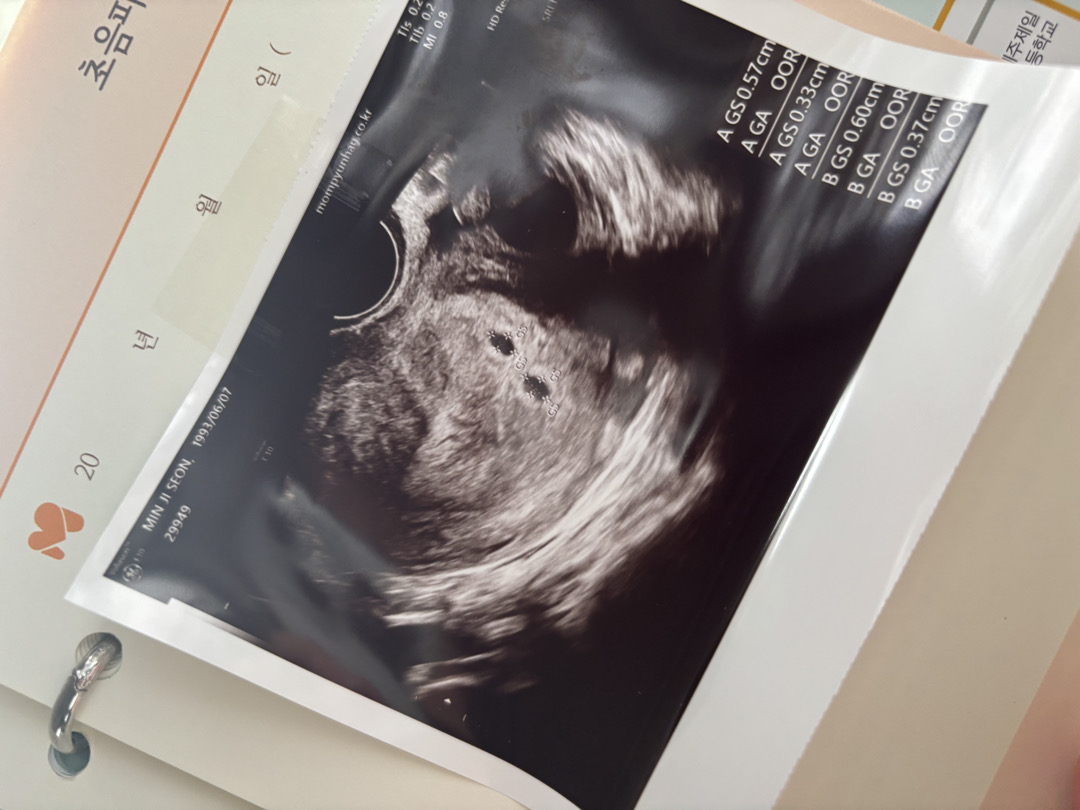

둘째 시험관 햇는데 둘다 착상되어서 쌍둥이맘이되었어요 둘째도 오고 셋째도 왔네여^^